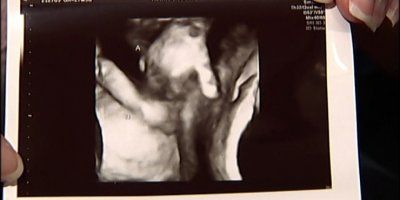

Otac je kazao i kako je tijekom drugog pregleda u siječnju vidio djevojčice kako se grle.

Ova priča se našla na naslovnicama širom svijeta i ostavila je doktore zapanjene.

Prije par tjedana, 4. siječnja, Anthea Jackson-Rushford iz Melbourna rodila je blizance.